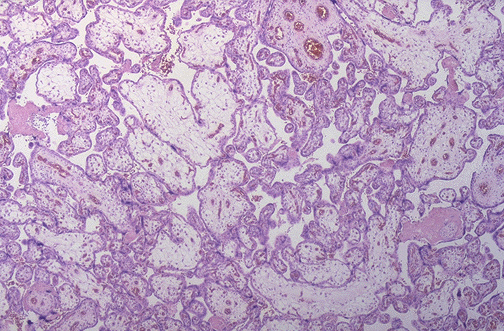

| Hydrops of the placenta, as shown here, almost always accompanies fetal hydrops. Causes for fetal hydrops may include fetal anemia, fetal cardiac disease, congenital anomalies, and congenital infections, but there are a multitude of potential causes for hydrops. |